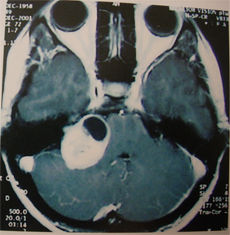

臨床表現為視力視野障礙,影像學檢查可見鞍區病變,蝶鞍骨質變化。如有內分泌表現診斷一般不難,需和顱咽管瘤、腦膜瘤、動脈瘤等鑑別,MRI對發現微腺瘤很有意義。

垂體瘤診斷方面,影像學檢查是非常重要的手段。其中以鞍區的核磁共振(MRI)檢查對垂體瘤的檢出率最高。通過鞍區薄層(每1mm掃描一層)增強影像的MRI檢測,若結合動態造影MRI檢測,直徑小至2-3mm的垂體微腺瘤也可以顯像。鞍區增強CT顯像對於部分垂體大腺瘤顯像效果好,可以了解鞍底骨質的破壞程度以及蝶竇氣化的程度。